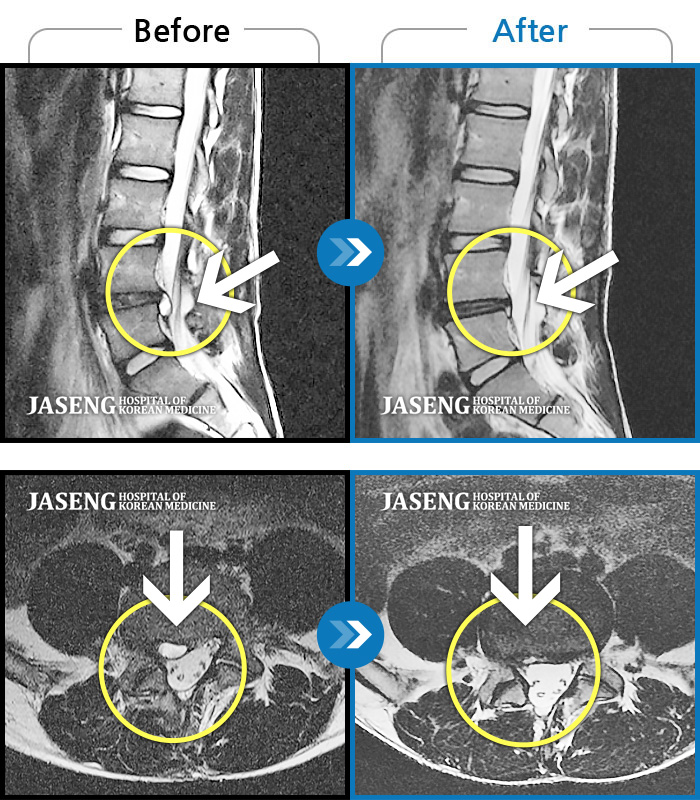

MRI 치료사례

허리디스크

부천 · 신동재 원장

의자 위를 여러 번 올라갔다 내려갔다 반복한 뒤 극심한 하요부 통증 및 좌측 하지부 저림

촬영시기

2024.06.22 ~ 2024.11.19